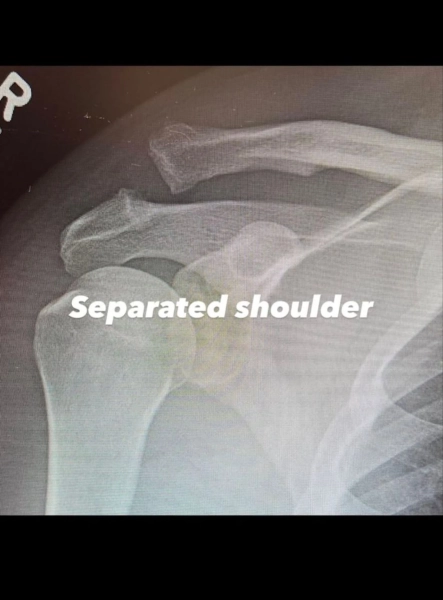

Американський актор Ченнінг Татум пройшов хірургічне втручання у зв’язку з дислокацією акроміально-ключичного зчленування. Він розмістив фотографію та рентгенівські зображення, запевнивши прихильників у своїй рішучості відновитися.

Як стало відомо, хірургія була необхідна через вивих акроміально-ключичного суглоба. Аби повернути плече у правильне положення, лікарям довелось вдатися до хірургічного втручання.

Окрім того, актор оприлюднив рентгенівські знімки плеча до та після проведення операції. Ченнінг Татум не повідомив обставини отримання ушкодження, однак запевнив, що налаштований здолати перешкоди та повністю зцілитися.